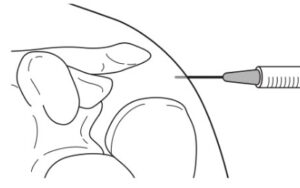

| 検査 | 【身体所見】 apprehension test:肩関節外転外旋位で水平外転し肩がはずれそうな不安感で陽性 【画像検査】 ①X線:左右の肩の画像を撮像、正常は上腕骨頭と関節窩が赤線のように適合している(右)が、脱臼すると適合が見られない(左) ②CT:Hill-sachs lesion、Bankart lesionの評価 ③MRI:関節唇や腱板などの軟部組織の損傷の評価、occult fractureの評価 |

| 整復 | 【徒手整復法】以下の順に整復トライ ①肩関節注射:20cc注射器にキシロカイン®を20cc吸引し、22Gで肩外側から正中に向けて15〜20cc注射する。 ②外旋法→Milch法:1人でも実施可能で、仰臥位で行う。 ③肩甲骨回旋+Stimson法:2人で実施する方法で、腹臥位で行う。筋肉質な人向け。 ④反対牽引法:静脈ルートを確保し、透視下で2人で実施する方法で、仰臥位で行う。⑤整復後はX線で確認する。 |